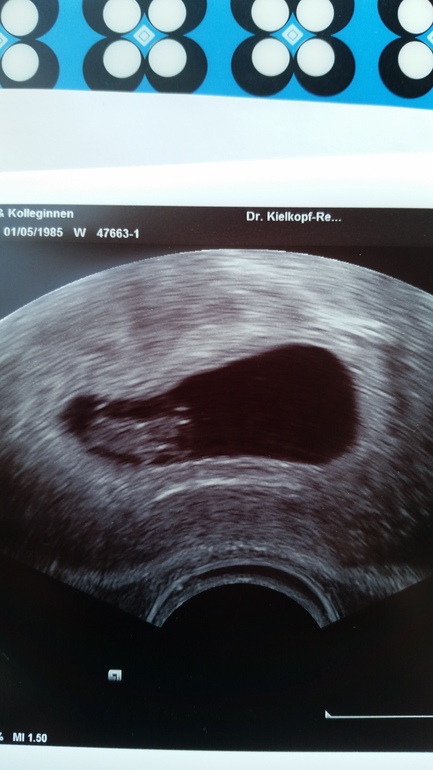

Беременность- 1 триместр ( только до 10 недель)ну вот и сходила я на узи ;) наш малышь выбрал самое удобное и безопасное место, в матке!!!! отклонений нет, сердечко стучит;) пдр поставили на 2 сентября.

желаю всем в скором времени пополнить свой семейный альбом вот такой фоточкой